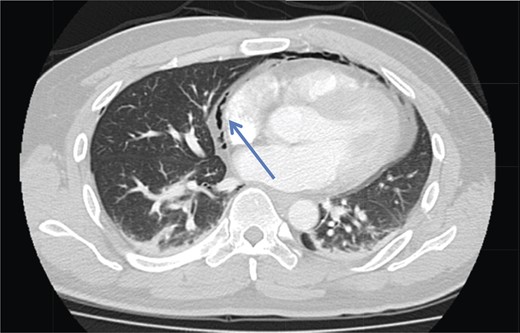

A 42-year-old male with a past medical history of hypertension was admitted for an elective TEP repair of his left inguinal hernia. Endotracheal intubation and general anesthesia were given uneventfully. The extraperitoneal space was developed with a balloon space maker, and insufflation of carbon dioxide at a maximum pressure of 12 mmHg was performed. Intraoperatively, a large incarcerated indirect left inguinal hernia containing omentum was reduced. A Optilene mesh (10 × 12 cm) was placed and tacked appropriately after hernia reduction. There were no obvious tears in the peritoneum and the total operative time was ∼90 min. No elevation of end-tidal CO2 was noted during the surgery and the patient was extubated successfully. The patient subsequently complained of left-sided chest pain on the same night of the surgery. He did not have abdominal pain. He had subcutaneous crepitus extending from the left groin to the left chest. His cardiac enzymes were negative and his electrocardiography revealed a sinus rhythm with no acute ischemic changes. A plain radiograph of the chest showed a sliver of lucency in the mediastinum suspicious for pneumomediastinum, with no obvious pneumoperitoneum or pneumothorax seen (Fig. 1). Computed tomographic (CT) imaging of the thorax and abdomen confirmed the radiograph finding of pneumomediastinum and diffuse subcutaneous emphysema tracking along the abdominal muscles bilaterally, as well as a small amount of free air and stranding in the left posterior pararenal space (Figs 2–4). The patient was treated conservatively with oral analgesia and supplemental oxygen. His chest pain resolved by the third postoperative day and he was discharged well. He was advised to avoid air travel for 1 month. He was reviewed in clinic at the 1-week and 1-month intervals and did not report any further chest pain or respiratory symptoms. His operation site healed well and he remained recurrence free.

Axial section CT pulmonary angiogram shows a pneumomediastinum (arrowhead).